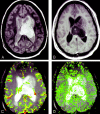

Background and purpose: Relative cerebral blood volume (rCBV) and vascular permeability (K(trans)) permit in vivo assessment of glioma microvasculature. We assessed the associations between rCBV and K(trans) derived from dynamic, susceptibility-weighted, contrast-enhanced (DSC) MR imaging and tumor grade and between rCBV and K(trans).

Methods: Seventy-three patients with primary gliomas underwent conventional and DSC MR imaging. rCBVs were obtained from regions of maximal abnormality for each lesion on rCBV color maps. K(trans) was derived from a pharmacokinetic modeling algorithm. Histopathologic grade was compared with rCBV and K(trans) (Tukey honestly significant difference). Spearman and Pearson correlation factors were determined between rCBV, K(trans), and tumor grade. The diagnostic utility of rCBV and K(trans) in discriminating grade II or III tumors from grade I tumors was assessed by logistic regression.

Results: rCBV was significantly different for all three grades (P </=.0005). K(trans) was significantly different between grade I and grade II or III (P =.027) but not between other grades or combinations of grades. Spearman rank and Pearson correlations, respectively, were as follows: rCBV and grade, r = 0.817 and r = 0.771; K(trans) and grade, r = 0.234 and r = 0.277; and rCBV and K(trans), r = 0.266 and r = 0.163. Only rCBV was significantly predictive of high-grade gliomas (P <.0001).

Conclusion: rCBV with strongly correlated with tumor grade; the correlation between K(trans) and tumor grade was weaker. rCBV and K(trans) were positively but weakly correlated, suggesting that these parameters demonstrate different tumor characteristics. rCBV is a more significant predictor of high-grade glioma than K(trans).